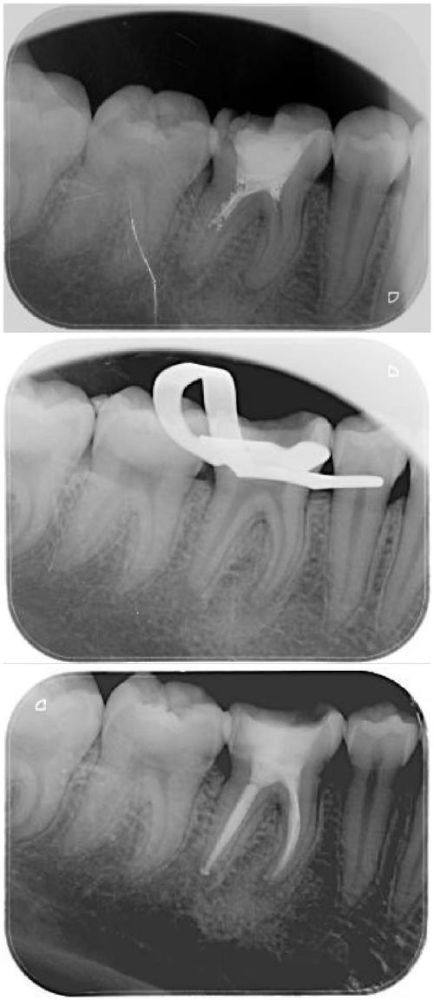

根管治疗是治疗牙髓炎、根尖周炎等牙髓疾病的常用方法,它就像是给牙齿做一次深度清洁和修复。一般来说,根管治疗需要分三次进行,每次治疗的目的和操作都不一样,这也导致了疼痛程度的差异。第一次治疗的主要任务是根管预备,医生会清理牙齿根管内发炎的牙神经;第二次是根管消毒,要扩大根管并清理内部残留物;第三次则是根管充填,使用牙胶尖配合根管糊剂将根管充填封闭。

到了第三次根管治疗,也就是根管充填阶段,疼痛感通常比较轻微。这是因为牙髓神经在前面的治疗中已经被清除了,而且填充过程相对简单。医生会使用牙胶尖配合根管糊剂将根管充填封闭,就像是给牙齿的内部空间做一个密封处理。整个过程不会对牙齿造成太大的刺激,所以患者一般不会感觉到特别疼。可以说,第三次治疗就像是一场“收尾战”,相对轻松。